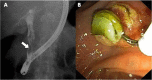

Hydatid disease is a worldwide zoonosis endemic in many countries. Liver echinococcosis accounts for 60-75% of cases and may be responsible for a wide spectrum of complications in about one third of patients. Some of these complications are potentially life-threatening and require prompt diagnosis and urgent intervention. In this article, we present our experience with common and uncommon complications of hepatic hydatid cysts which include rupture, bacterial superinfection, and mass effect-related complications. Specifically, the aim of this review is to provide key imaging features and diagnostic clues to guide the imaging diagnosis using a multimodality imaging approach, including ultrasound (US), computed tomography (CT), magnetic resonance (MR), and endoscopic retrograde cholangiopancreatography (ERCP).